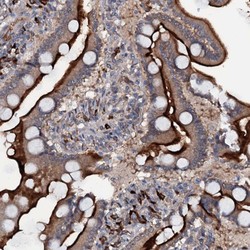

Supportive validation

- Submitted by

- Atlas Antibodies (provider)

- Main image

- Experimental details

- Immunohistochemical staining of human duodenum shows strong membranous positivity in glandular cells.